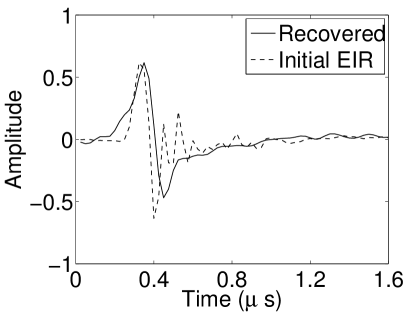

In Figure 17, the results corresponding to use of the 3D imaging model that incorporated SIR effects are shown. The EIR estimated by the VP algorithm is also shown. In Figure 18, images and EIRs reconstructed by use of the VP algorithm with different regularization parameters values are shown.

Similar to the case described above where the transducer SIR was neglected, these results reveal that use of the VP algorithm can produce images with a cleaner background and enhanced spatial resolution than yielded by use of a conventional iterative algorithm that employed the measured EIR. For example, detailed information regarding the vessels near the organ’s periphery was better preserved by the VP algorithm than by the conventional iterative algorithm. These images corroborate our assertion that the VP algorithm can significantly reduce the artifacts and distortions in the reconstructed image. It is also worth pointing out that, unlike the numerical phantom studies, the artifacts and distortions in the images may be caused not only by the inaccurate EIR but also by other factors, such as neglecting acoustic heterogeneities and the variation of the EIRs among the elements of the transducer array. In such cases, the EIR estimated by the VP algorithm represents an effective system impulse response that minimizes the inconsistency between the measured data and the imaging model.

VI-F Auto-focus capabilities

Conventional PACT reconstruction algorithms assume that the medium is described by a constant speed-of-sound (SOS) value. In practice, this value may not be known precisely and can be tuned [TVZL2011] to maximize the spatial resolution of the reconstructed images. The effect of an incorrect SOS value can sometimes be compensated for by use of the VP algorithm due to modification of the EIR during the joint estimation. Figures 19(a) and 19(b) show images reconstructed by use of the conventional iterative method and the VP algorithm, respectively, when different constant SOS values are assumed. The 2D imaging model that ignored the SIR was employed. Nearly identical images were reconstructed by use of the VP algorithm, even though the assumed SOS values were different in each case. The images contained reduced artifact levels as compared to those reconstructed by use of the conventional method. The recovered EIRs differed by a time shift (as displayed in Fig. 19(c)). Since the object was located near the center of the transducer array and was small compared to the radius of the array, the scaling effect due to the inaccurate SOS can be approximated by the shift of the EIR, which explains how the recovered EIR compensates for the error in SOS value.